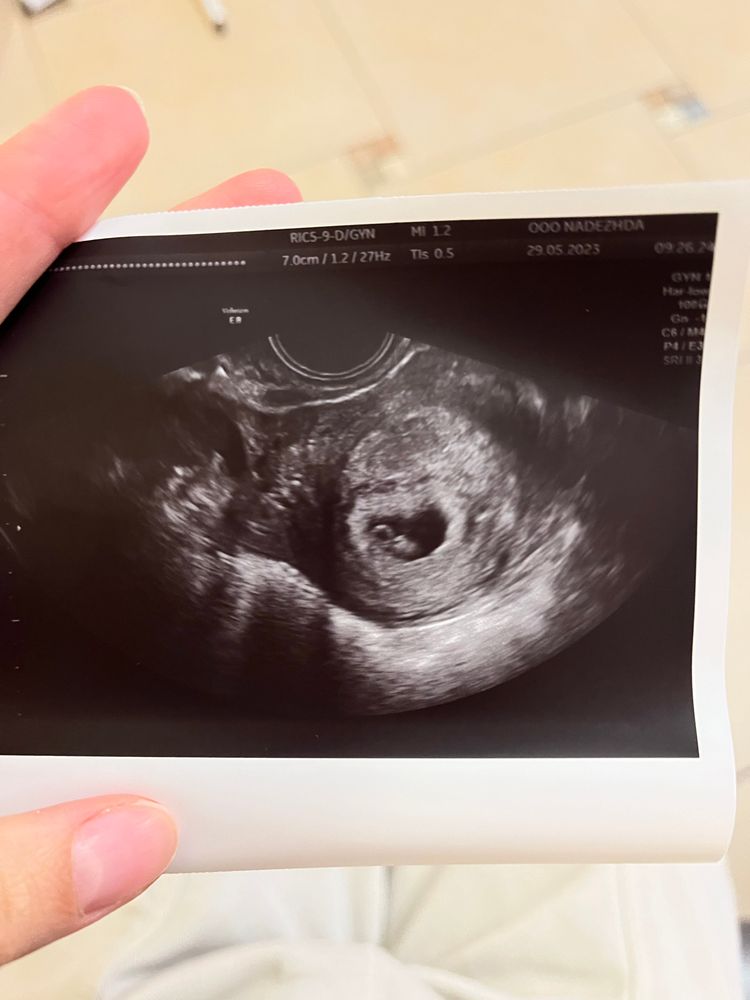

Изображение

Тут смотрите

Первый приём 7 недель и 4 дня 💓